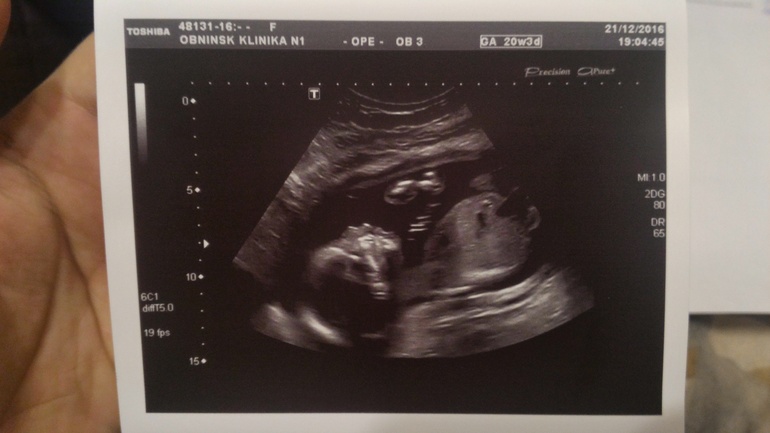

Сегодня 20 недель начались с похода на скрининг))) Нам там подтвердили сынульку, все с нами ттт хорошо, отклонений не выявлено по узи ставят 20+5 неделек) БПР -49мм , написали один живой плод в головном предлежании, плацента расположена по передней и задней стенкам левому ребру, лежим мы поперек маминого животика и я это прекрасно чувствую, буянит сын) головка справа,попка слева ))) Кол-во вод в норме шейка матки 39 мм)

В общем все хорошо и я счастлива) По состоянию все гуд, иногда только тянет связки по бокам, и то что он вытягивается когда лежит поперек доставляет дискомфорт конечно, но не такой уж и сильный) А так все замечательно)) ну и вот наш профиль и засняли нам наше достоинство)) и фотопузик)))